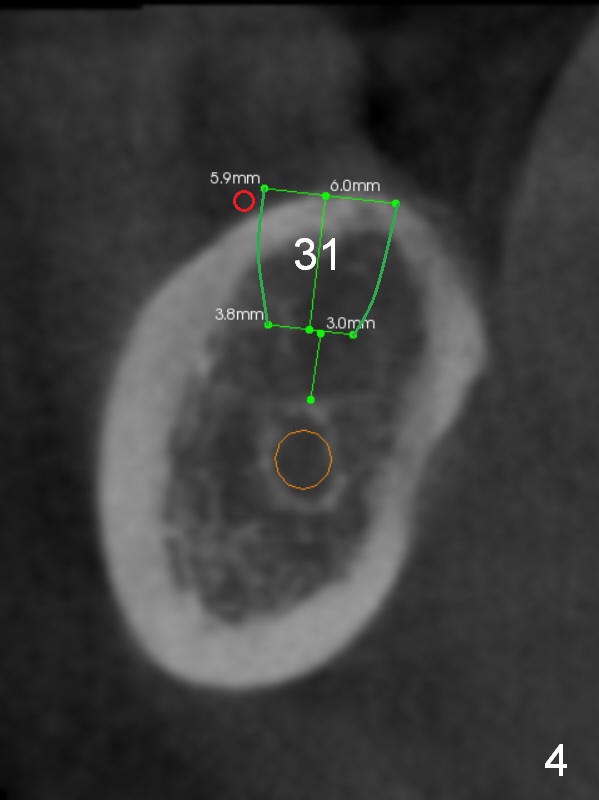

Fig.2 (sagitttal section) shows that the bone height at the site of #31 is shorter than that of #30. There is a 1 mm separation from the Inferior Alveolar Nerve (brown) if a 8 mm implant is placed at #31 (Fig.2,3 (coronal section)), whereas 3 mm separation for a 6 mm implant (Fig.4). Since the tooth #2 is supraerupted, the shorter implant at #31 is more appropriate. It is placed a little deeper (Fig.4' arrow) so that the abutment or the opposing tooth does not need to be trimmed too much. In addition, choose a widest abutment (purple, e.g., 7.8 mm) with the shortest cuff (pink, 1 mm). A splinted immediate provisional will be fabricated to prevent the gingiva from growing into the abutment margin. At restorative phase, a smaller abutment will be used (e.g., 5.8 mm) so that the gingiva is clear from the margin. It will be easy for impression. Then the provisional will be relined to keep the gingiva from growing into the space just created by changing abutments. Bone graft will be needed buccal to the implant at #31 (Fig.3,4 red circle; L: lingual).